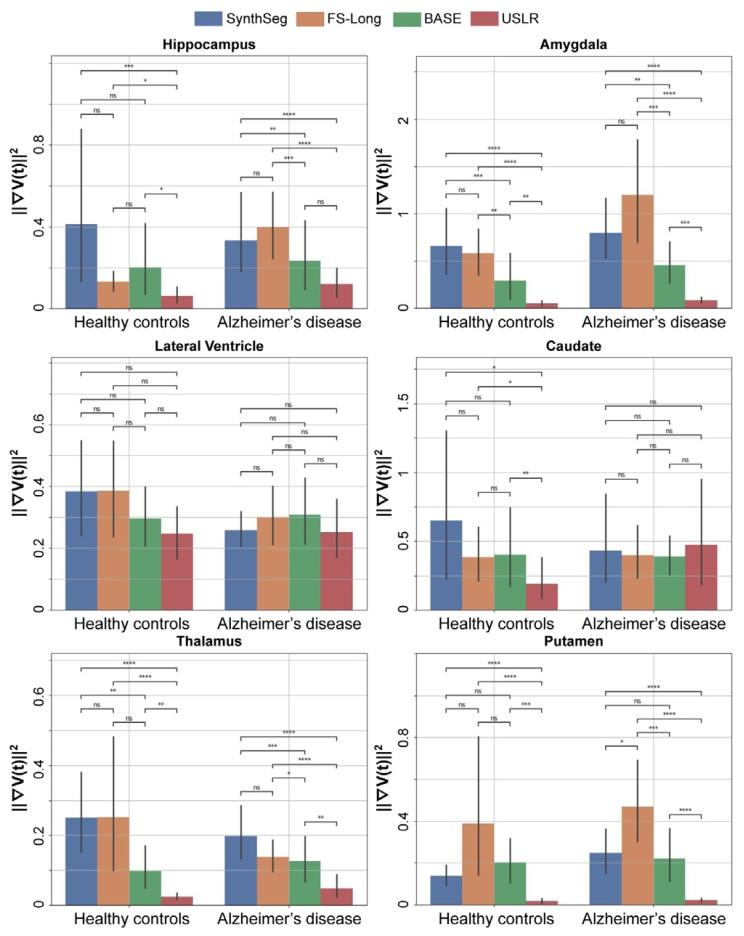

Fig. 3. Evaluating trajectory smoothness using Eq. (18) stratified by diagnosticcategory. We compare four different models: SynthSeg, longitudinal Freesurfer segmentations (FS-Long), longitudinal refinement using the baseline image as template(BASE) and USLR. Significant differences in smoothness are found in a Wilcoxon-ranktest between methods for (*) 1 ⋅ 10−2 < 𝑝 < 5 ⋅ 10−2 , () 1 ⋅ 10−3 < 𝑝 < 1 ⋅ 10−2 , (*)1 ⋅ 10−4 < 𝑝 < 1 ⋅ 10−3 and () 𝑝 < 1 ⋅ 10−4 thresholds

图3 采用公式(18)按诊断类别分层评估轨迹平滑度。我们比较了四种不同模型:SynthSeg、纵向FreeSurfer分割(FS-Long)、以基线图像为模板的纵向优化(BASE)以及USLR。通过Wilcoxon秩检验发现,不同方法间的平滑度存在显著差异,显著性水平标注如下:()1×10⁻²<𝑝<5×10⁻²,(**)1×10⁻³<𝑝<1×10⁻²,(**)1×10⁻⁴<𝑝<1×10⁻³,()𝑝<1×10⁻⁴。